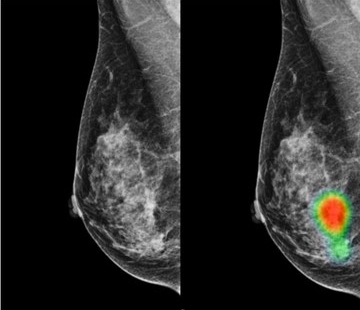

Lunit INSIGHT MMG анализирует маммографические снимки с точностью до 97%, обеспечивая локализацию участков, подозрительных с точки зрения рака молочной железы. Она также оценивает аномалии, отражая вероятность наличия в этих местах раковых поражений.